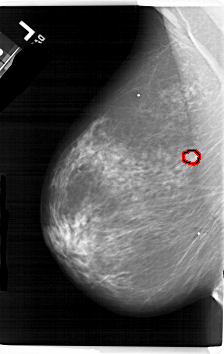

A_1657_1.RIGHT_MLO

RIGHT_MLO LINES 6871 PIXELS_PER_LINE 4036 BITS_PER_PIXEL 12 RESOLUTION 43.5 NON_OVERLAY

ABNORMALITY 1

LESION_TYPE MASS SHAPE LOBULATED MARGINS OBSCURED

ASSESSMENT 4

SUBTLETY 3

PATHOLOGY MALIGNANT